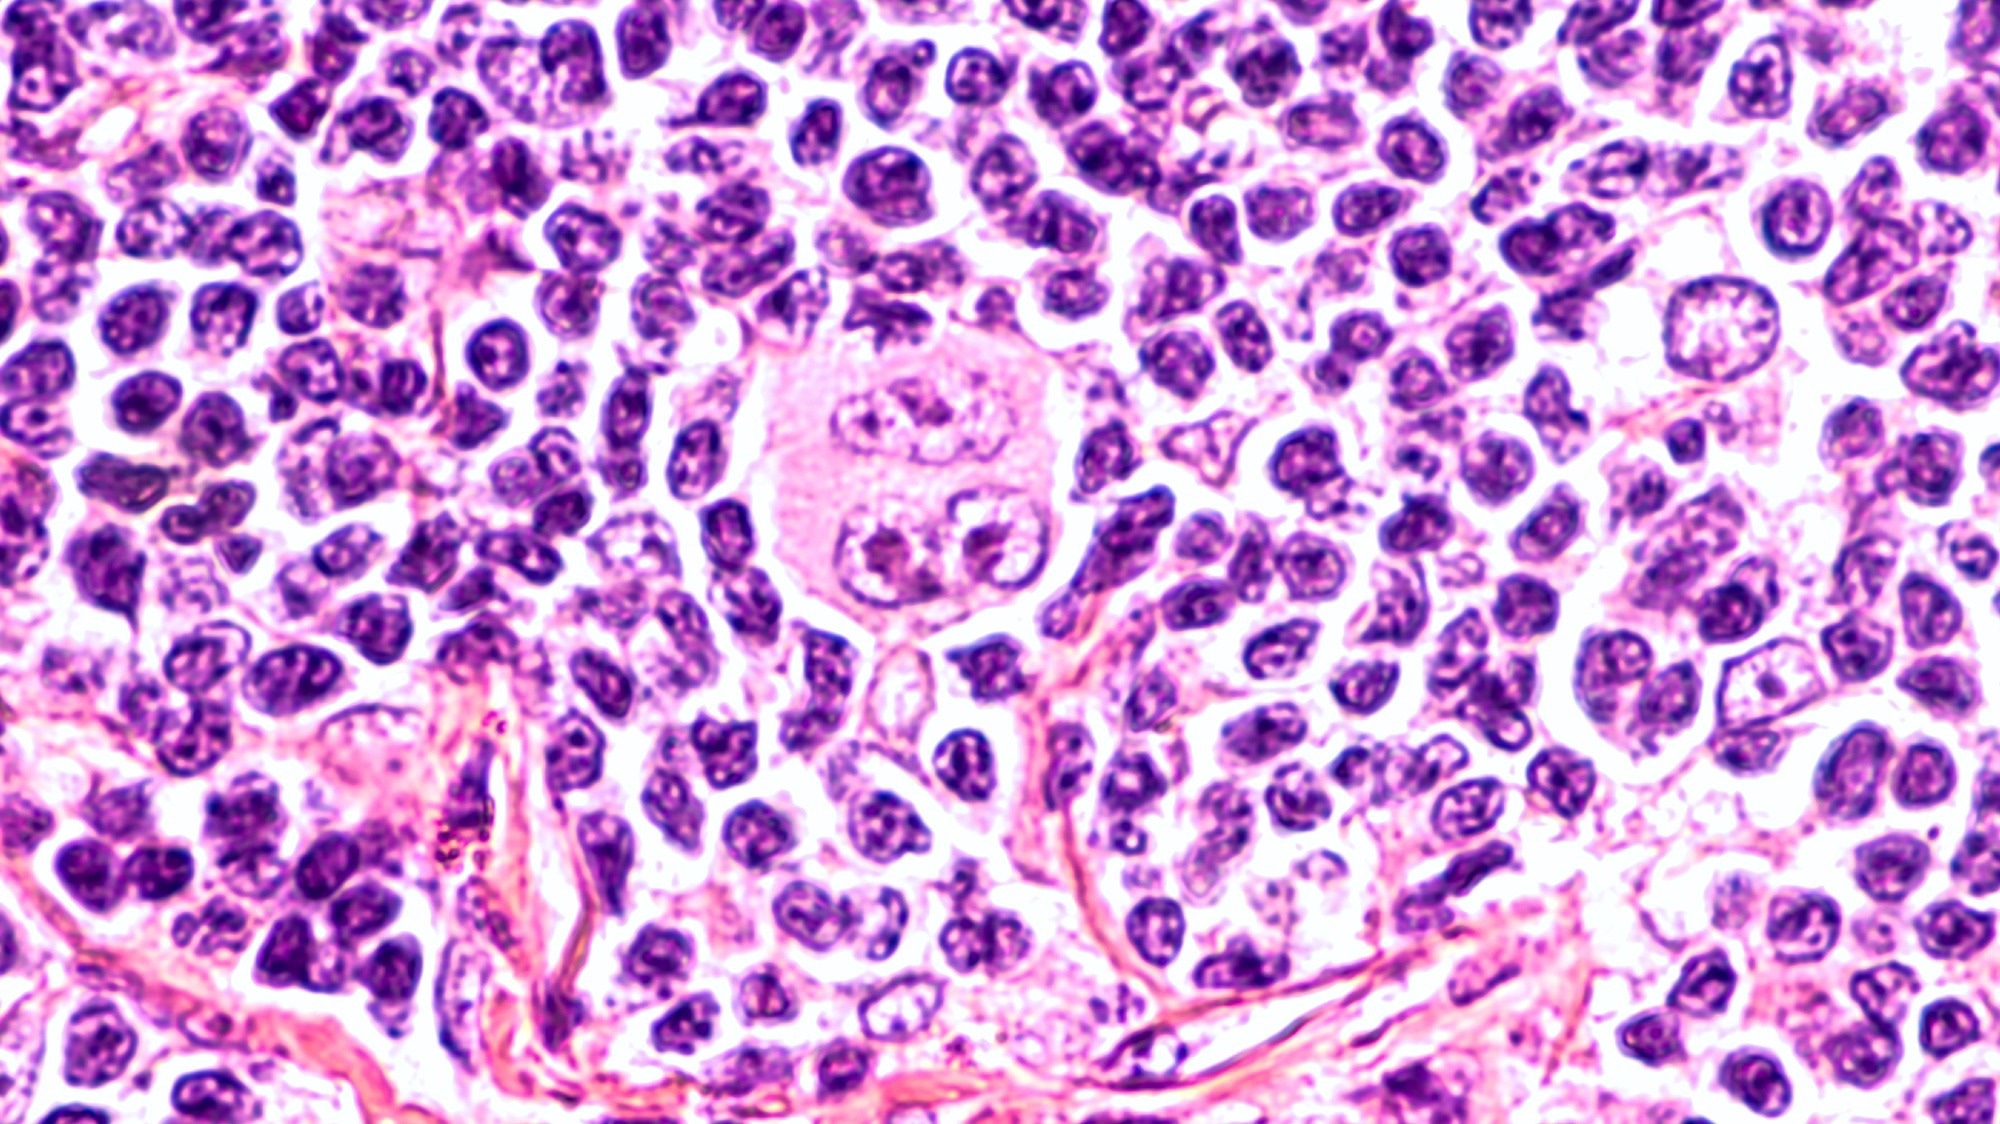

Photomicrograph of a lymph node in a patient with HodgkinPhotomicrograph of a lymph node in a patient with Hodgkin's Disease (lymphoma), showing a Reed Sternberg cell variant. Image Credit: David A Litman / Shutterstock

In cHL, tumor cells are primarily comprised of Reed-Sternberg (RS) cells that originate from mature B-cells. Despite this origin, RS cells typically appear much larger than B-cells due to the presence of multiple nuclei.